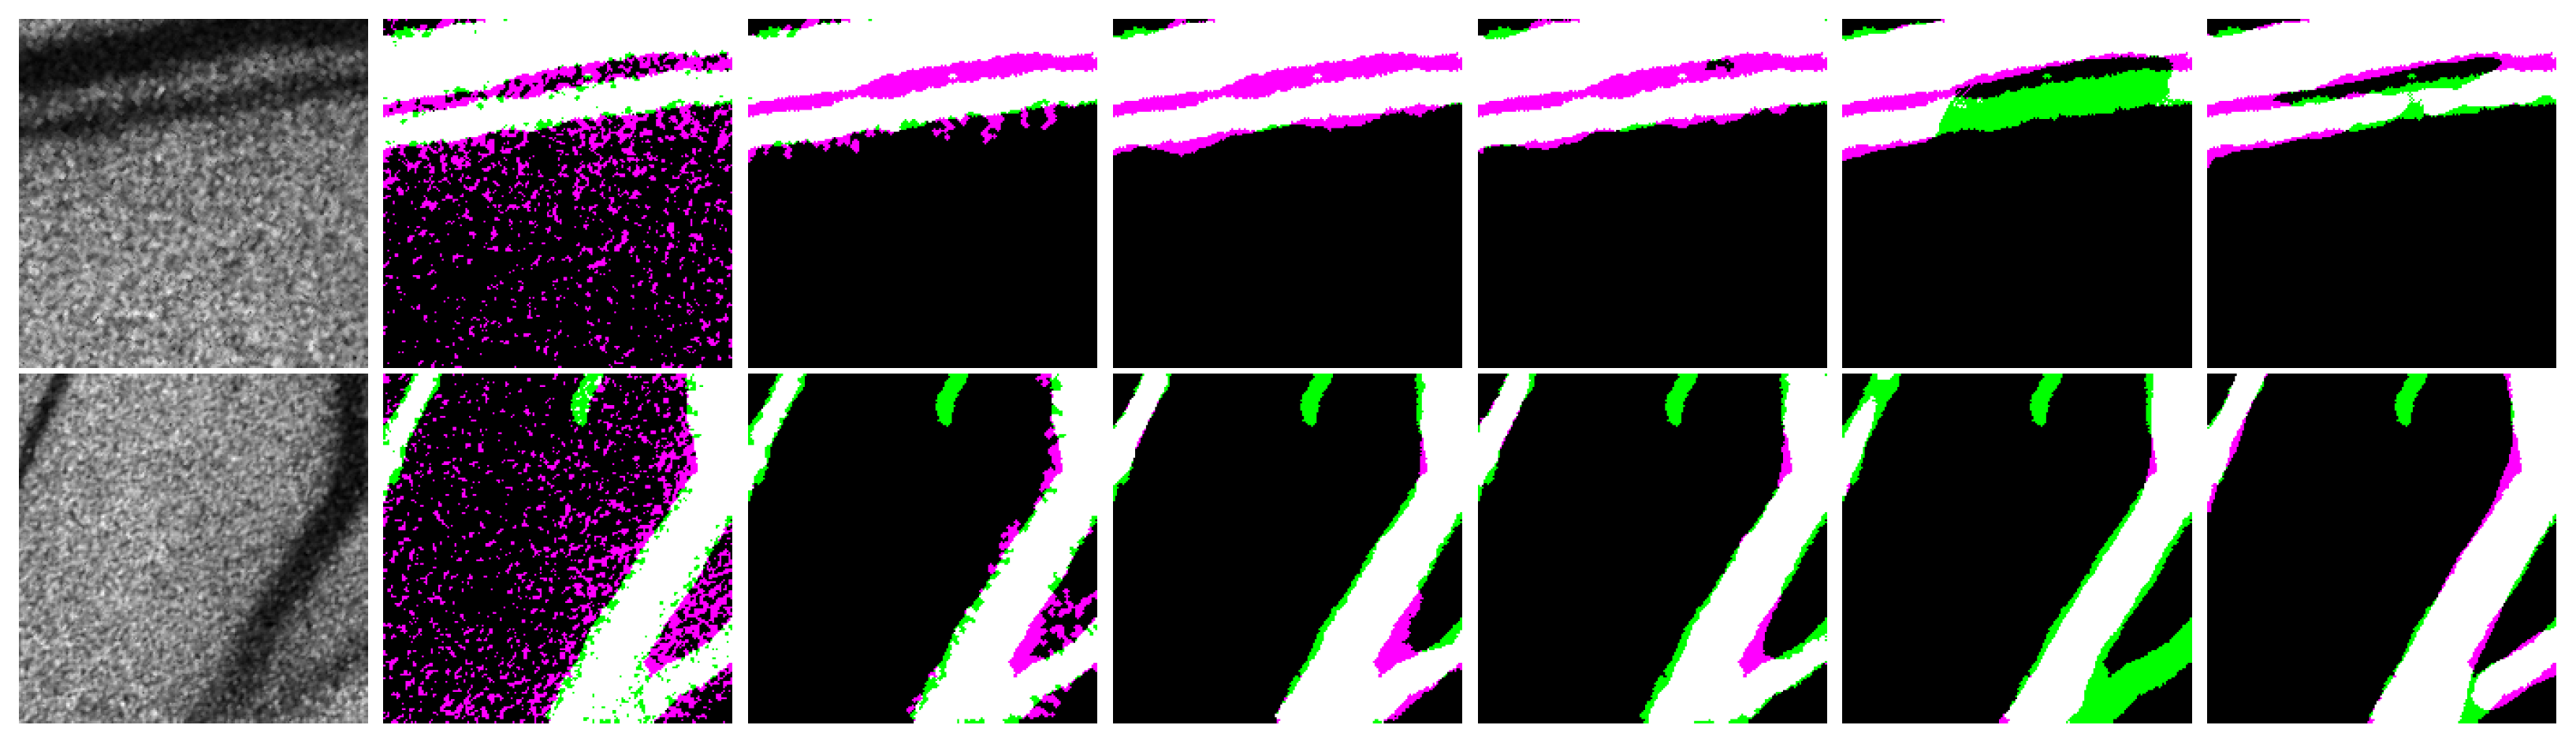

Representative in vivo images of the dataset used for validation of the segmentation methods are shown in Figure 5. This qualitative analysis is performed in the test set because in the in vitro images, the difference is less noticeable because the models were trained on it. This analysis is performed to know the generalization capabilities in this set unseen by the models during the training. As can be seen, the traditional image processing methods, global and k-means, often over-segment the image because of the noise and the combined information in the periphery of the blood vessel, for the case of the morphological approach. On the other hand, machine learning and deep learning methods alleviated the blob problem but with low sensibility as its main drawback. It is important to note that the trained models did not use images of tissue surrounded by blood vessels, as in the case shown in Figure 5, but the R-UNet + ET + LA segmentation was learned to locate blood vessels, improving the spatial resolution in the segmentation results.

Figure 5.

Two in vivo representative RSIs and their corresponding segmentation varying the algorithm. From left to right: RSI, global, k-means, morphological k-means with features, UNet, UNet + ET + LA, R-UNet, and R-UNet + ET + LA.